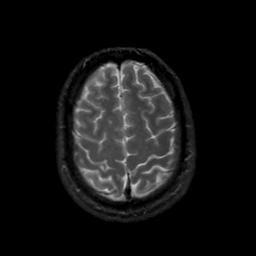

MR Study #18, July 21, 1991 -- Slice #41